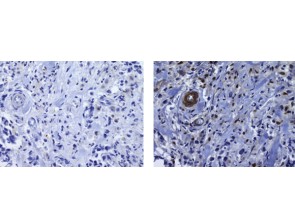

Description: The monoclonal phpu13 recognizes human and mouse PU.1, a member of the ets family of transcription factors. This 42 kDa protein was originally identified as Spi-1, a proto-oncogene, for its role in Friend virus-induced murine erythroleukemia. Expression of PU.1 plays a critical role in lymphocyte and myeloid development. Knock-out mice are neonatal lethal and lack myeloid, T and B cells. In addition erythroid development is also altered. Protein expression levels help guarantee proper development; higher levels in myeloid cells compared to lymphocytes. PU.1 controls transcription of several proteins including CD11b, CD18, Gata2, IRF4, CD20, CD10, and CD79.

Disruption of PU.1 expression may play a role in several specific leukemias; such as B-chronic lymphocytic leukemia, mantle cell lymphoma, follicular lymphoma, marginal zone lymphoma, Burkitt lymphoma, diffuse large cell lymphoma, diffuse large B-cell lymphoma, T-cell rich B-cell lymphoma, and nodular lymphocyte predominant Hodgkin.